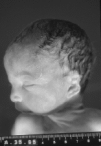

El informe autópsico es el siguiente: Feto hembra de treinta semanas de gestación, según peso y longitudes occipito-sacra y del pie, que presenta inmadurez visceral grado II, polimalformado, presentando anomalías faciales, hipoplasia pulmonar (índice peso corporal/peso pulmonar = 0,007), surco simiesco bilateral, bazo supernumerario (0,3 cm) y quiste simple subcapsular hepático (0,2 cm). Las anomalías faciales son las siguientes: Asimetría del tercio facial inferior, con hipoplasia mandibular y de zigoma derechos, microotia derecha con implantación baja de conducto auditivo externo, discreto hipertelorismo, atresia de coanas bilateral, anquiloglosia y paladar ojival con fisura palatina mucosa (ver imágenes adjuntas).

| Figuras 3A, 3B, 3C. |